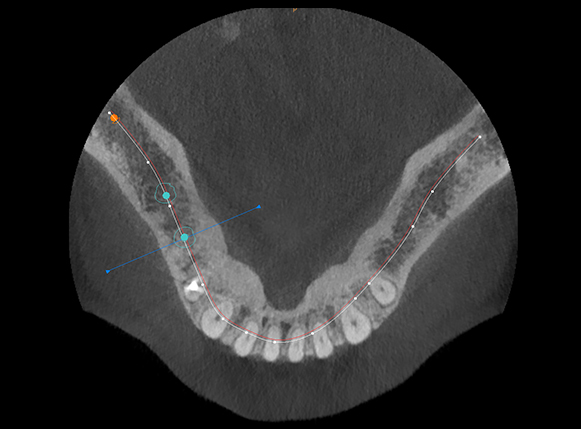

術前のCTでのシュミレーション

インプラント手術を安全に行うためには「従来の2次元のレントゲン」 だけではなく、「三次元レントゲン(歯科用CT)」が必須です。

当院ではインプラント治療に関しては必ずCT撮影を行い、事前に診査・診断を行います。(インプラント相談と治療の際のCT撮影は無料。通常12,000円(税別))

オレンジ色で示した部分が「下顎管」といって、顎の大事な「神経と血管」 が走行しています。これを傷つけてしまうと麻痺などの偶発症を引き起こすことがあります。

当院では適切な位置にインプラントを埋入するためにCT撮影とステント(埋入方向を定める装置) を使用し、より安全に手術を行うことに努めておりますので安心して治療を受けて頂くことが可能です。

術後に適切な位置に埋入完了

術後のCT画像からも、シミレーション通り適切な位置にインプラントを埋入出来ていることが確認できます。